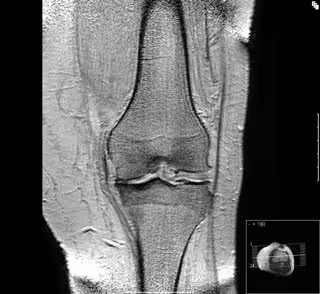

Artrosis de rodilla

Como ha recordado Climent durante el taller titulado 'Intervencionismo Básico GETRI 1: Ecografía de Rodilla. Cara anterior y medial', la artrosis es una enfermedad crónica y degenerativa de la rodilla que aparece cuando se pierde o deteriora el cartílago articular y esa desintegración del cartílago hace que los huesos se rocen entre sí, lo que con el paso del tiempo, provoca rigidez, dolor, inflamación y disminución de la movilidad.

Además de la artrosis, existen muchas otras patologías y problemas que afectan a la rodilla como las lesiones de tendones o ligamentos y, en este sentido, la incorporación de la ecografía al tratamiento de rodilla ha permitido mejorar su diagnóstico. "La ecografía permite dar un paso más en el diagnóstico porque estudia la articulación y confirmar las sospechas de lesión. Incluso, puede determinar la utilidad de realizar una infiltración terapéutica con medicación para ayudar a resolver el problema. Todo ello, en una sola consulta", ha explicado Climent.